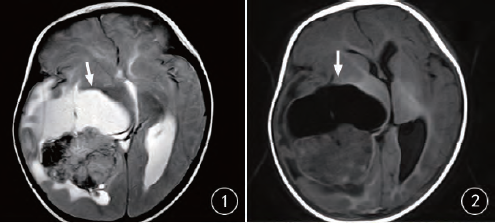

橫紋肌樣瘤是一種罕見(jiàn)的腫瘤,但生命綠洲卻憑借其獨(dú)特的醫(yī)療視角和先進(jìn)的設(shè)備,走在治療的前沿,這里采用的治療技術(shù)不僅結(jié)合了傳統(tǒng)手術(shù)的優(yōu)勢(shì),還融入了最新的生物技術(shù)、基因療法和免疫治療等前沿科技,經(jīng)驗(yàn)豐富的醫(yī)療團(tuán)隊(duì)緊跟國(guó)際醫(yī)學(xué)的最新進(jìn)展,不斷嘗試將最新的研究成果應(yīng)用到臨床實(shí)踐中。